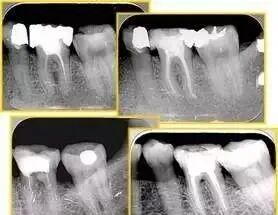

定义:根管内壁上人为产生的不规则形状阻止器械顺利进入根尖。

原因:器械没有预弯,根向压力过大。

右图箭头处示台阶形成

牙胶尖什么颜色最全整理 | 根管治疗标准步骤和细节把握_https://www.jmylbn.com_新闻资讯_第37张

1. 根尖拉开

( 1 )定义:弯曲根管根尖拉直造成根尖位置的改变。

出现台阶可造成根尖拉开,根管治疗需进行根管填充时根管三维充填占满困难。

( 2 )原因:器械没有预弯,弯曲根管过多使用旋转力。